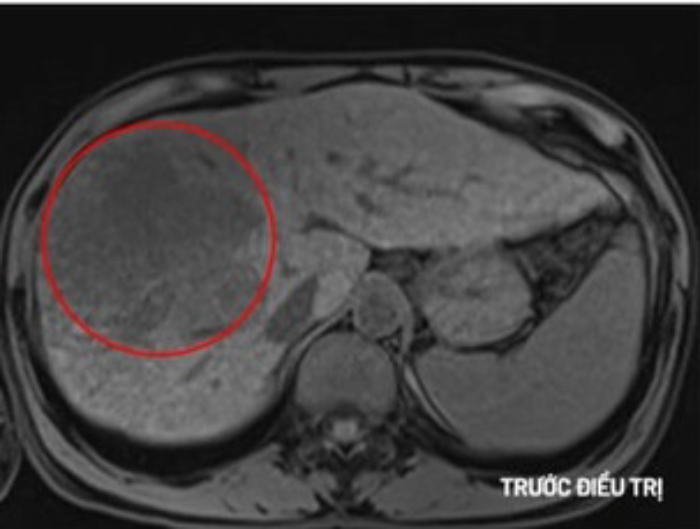

Xét nghiệm AFP cao bất thường nên các bác sĩ làm xét nghiệm chuyên sâu. Kết quả chụp MRI cho thấy khối u lớn ở gan phải với kích thước 10x10x12cm. Bác sĩ chẩn đoán anh C. mắc ung thư gan giai đoạn muộn.